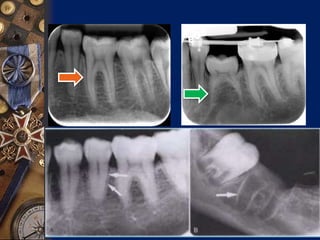

Radiographic Features

Partial absence of periodontal ligament.

A break in continuity of PDL ,

indicating an area of ankylosis is usually

evident

Loss of lamina Dura

Radiographic Features Partial absenceof periodontal ligament. A break in continuity of PDL , indicating an area of ankylosis is usually evident